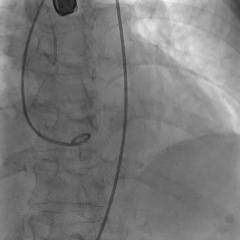

术中影像

输送器过弓

snare辅助下跨瓣